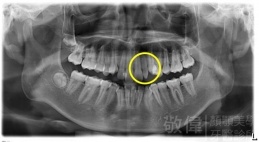

| 6 | 前牙美容 | 矯正+牙齦增補+晶鑽全瓷冠 | ||

| 7 | 前牙美容 | 矯正+晶鑽全瓷冠 | ||

| 8 | 前牙美容 | 快速矯正之美容晶瓷貼片及晶鑽瓷冠 | ||

| 9 | 前牙美容 | 矯正+美容晶瓷貼片 | ||

| 10 | 前牙美容 | 快速矯正之牙冠增長術+美容晶瓷貼片 |